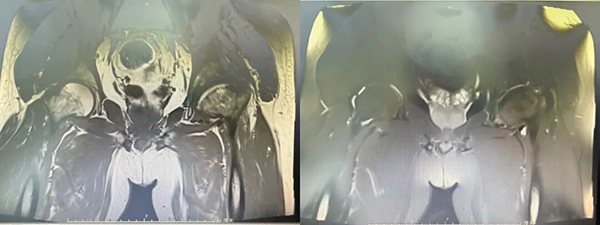

术前MRI:

来到生态城医院骨科后,检查结果揭开了真相:左侧股骨头缺血性坏死(ARCO分期Ⅳ期)——股骨头已经塌陷变形,保守治疗已无能为力。